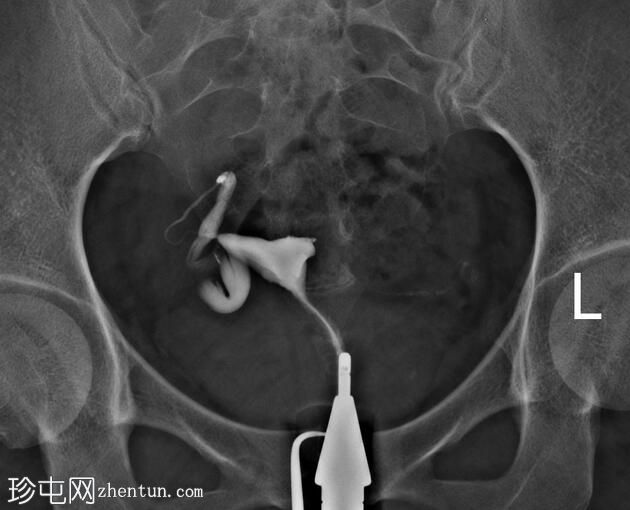

子宫体位于盆腔右侧旁中线,形态及轮廓正常。

宫颈管长度及黏膜表面正常,扩张正常。

右侧输卵管充盈,呈逐渐扩张,内有造影剂残留,无因输卵管积水导致的造影剂溢出。

左侧输卵管出现腹膜溢出。